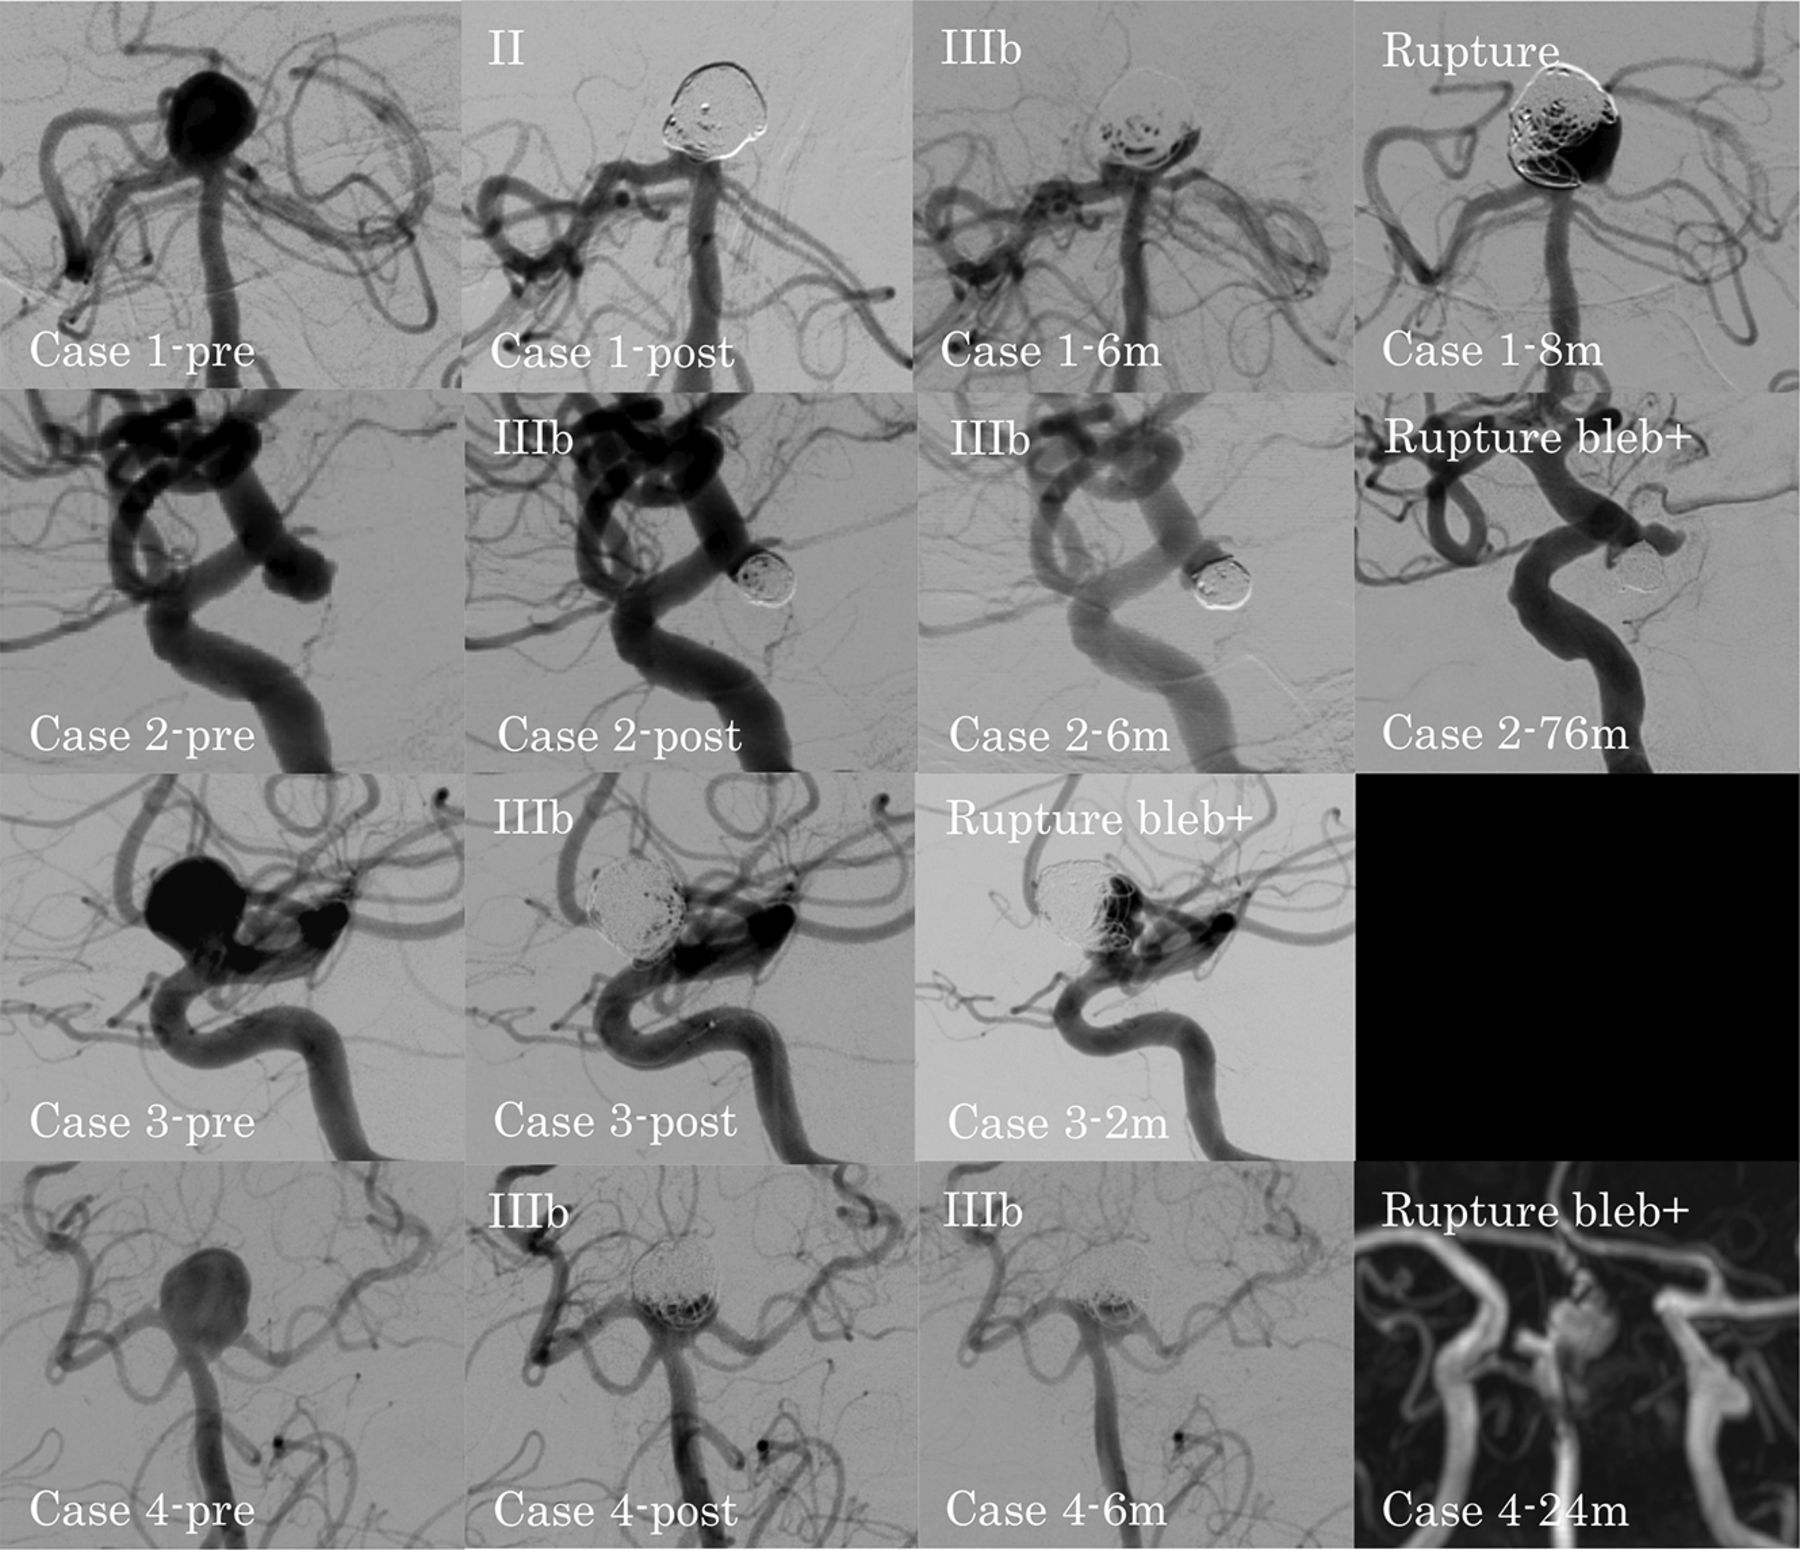

The cases of ruptured recanalized aneurysm are summarized in the On-line Table. The DSA findings of ruptured recanalized aneurysms in the unruptured and ruptured groups are shown in Figs 2 and 3, respectively. In patient 4 in the unruptured group, DSA could not be performed when the recanalized aneurysm ruptured. Thus, the MRA findings are shown instead. In the unruptured group, 4 recanalized aneurysms ruptured. In patient 1 with a large basilar artery–bifurcation aneurysm, the type of recanalization changed from class II to IIIb, and the aneurysm ruptured at 8 months after coil embolization. In patient 2 with an ICA–postrior communicating artery (PcomA) aneurysm, patient 3 with an ICA–paraclinoid aneurysm, and patient 4 with a large basilar artery–bifurcation aneurysm, the type of recanalization was class IIIb, and the aneurysms ruptured with a new bleb formation at 76 , 2, and 24 months after coil embolization, respectively. All 4 patients with ruptured recanalized aneurysms were receiving continued antiplatelet therapy at the time of rupture.

DSA findings for ruptured recanalized aneurysms in the unruptured group. Case 1-pre: preprocedural basilar artery–bifurcation aneurysm; case 1-post: class II aneurysm occlusion immediately after the procedure; case 1–6m: class IIIb recanalization at 6 months after the procedure; case 1–8m: ruptured recanalized aneurysm at 8 months after the procedure; case 2-pre: preprocedural ICA–posterior communicating artery aneurysm; case 2-post: class IIIb aneurysm occlusion immediately after the procedure; case 2–6m: progression of the class IIIb recanalization at 6 months after the procedure; case 2–76m: ruptured recanalized aneurysm with a new bleb at 76 months after the procedure; case 3-pre: preprocedural paraclinoid-ICA aneurysm; case 3-post: class IIIb aneurysm occlusion immediately after the procedure; case 3–2m: ruptured recanalized aneurysm with a new bleb at 2 months after the procedure; case 4-pre: preprocedural basilar artery–bifurcation aneurysm; case 4-post: class IIIb aneurysm occlusion immediately after the procedure; case 4–6m: no change at 6 months after the procedure; case 4–24m: MRA shows the ruptured recanalized aneurysm with a new bleb at 24 months after the procedure.